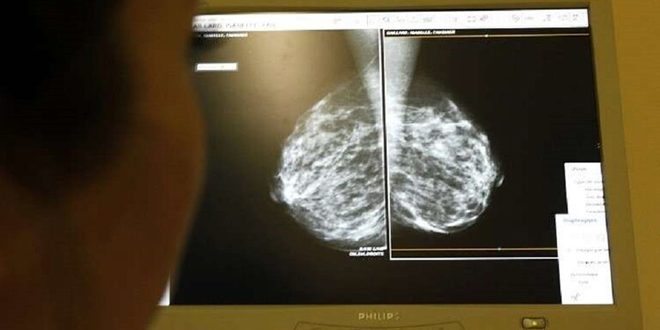

كشفت دراسة بريطانية حديثة أنه بات بالإمكان تجنيب آلاف النساء اللائي يخضعن لجراحة سرطان الثدي عمليات متكررة وذلك بفضل بذرة مغناطيسية صغيرة تزرع داخل الورم.

ووفقا لصحيفة ديلي ميل البريطانية فقد أوضحت الدراسة التي أجراها مجموعة من الباحثين بمستشفى جامعة ساوث مانشستر أن النساء اللائي يخضعن لجراحة سرطان الثدي يحتاجون بنسبة 25 بالمئة لإجراء جراحة ثانية حيث يعد ذلك ضروريا في حال عدم استئصال الورم بشكل كامل في الجراحة الأولى مضيفة أن 6 بالمئة فقط من المرضى الذين زرع لهم جهاز “ماكسيد” الصغير احتاجوا إلى جراحة ثانية كونه ساعد على تحسين الدقة أثناء العملية الأولى.

وأشارت الدراسة إلى أن التقنية الجديدة تعمل عن طريق وضع المريض تحت تأثير المخدر الموضعي باستخدام الموجات فوق الصوتية أو الماموغرام ثم يقع إدخال جهاز بحجم 5 مم مصنوع من الصلب الطبي باستخدام إبرة طويلة.

وبينت الدراسة أنه وأثناء العملية اللاحقة لإزالة الورم يستخدم الجراح مسبارا يصدر مجالا مغناطيسيا وصوتا عالي النغمة عندما يقترب من البذرة وعلى خلاف تقنية أسلاك يوم الجراحة فإن التقنية الجديدة تخفض من جود ندبات في الصدر وتكون هناك فتحة صغيرة فقط تحت الذراع حيث يتم إزالة الغدد الليمفاوية.